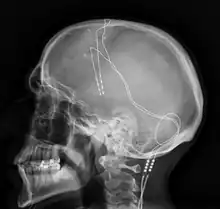

The DBS system consists of three components: the implanted pulse generator (IPG), the lead, and an extension. The IPG is a battery-powered neurostimulator encased in a titanium housing, which sends electrical pulses to the brain that interfere with neural activity at the target site. The lead is a coiled wire insulated in polyurethane with four platinum-iridium electrodes and is placed in one or two different nuclei of the brain. The lead is connected to the IPG by an extension, an insulated wire that runs below the skin, from the head, down the side of the neck, behind the ear, to the IPG, which is placed subcutaneously below the clavicle, or in some cases, the abdomen.[9] The IPG can be calibrated by a neurologist, nurse, or trained technician to optimize symptom suppression and control side effects.[36]

DBS leads are placed in the brain according to the type of symptoms to be addressed. For non-Parkinsonian essential tremor, the lead is placed in either the ventrointermediate nucleus of the thalamus or the zona incerta;[37] for dystonia and symptoms associated with PD (rigidity, bradykinesia/akinesia, and tremor), the lead may be placed in either the globus pallidus internus or the subthalamic nucleus; for OCD and depression to the nucleus accumbens; for incessant pain to the posterior thalamic region or periaqueductal gray; and for epilepsy treatment to the anterior thalamic nucleus.

All three components are surgically implanted inside the body. Lead implantation may take place under local anesthesia or under general anesthesia ("asleep DBS"), such as for dystonia. A hole about 14 mm in diameter is drilled in the skull and the probe electrode is inserted stereotactically, using either frame-based or frameless stereotaxis.[38] During the awake procedure with local anesthesia, feedback from the person is used to determine the optimal placement of the permanent electrode. During the asleep procedure, intraoperative MRI guidance is used for direct visualization of brain tissue and device.[39] The installation of the IPG and extension leads occurs under general anesthesia.[40] The right side of the brain is stimulated to address symptoms on the left side of the body and vice versa.